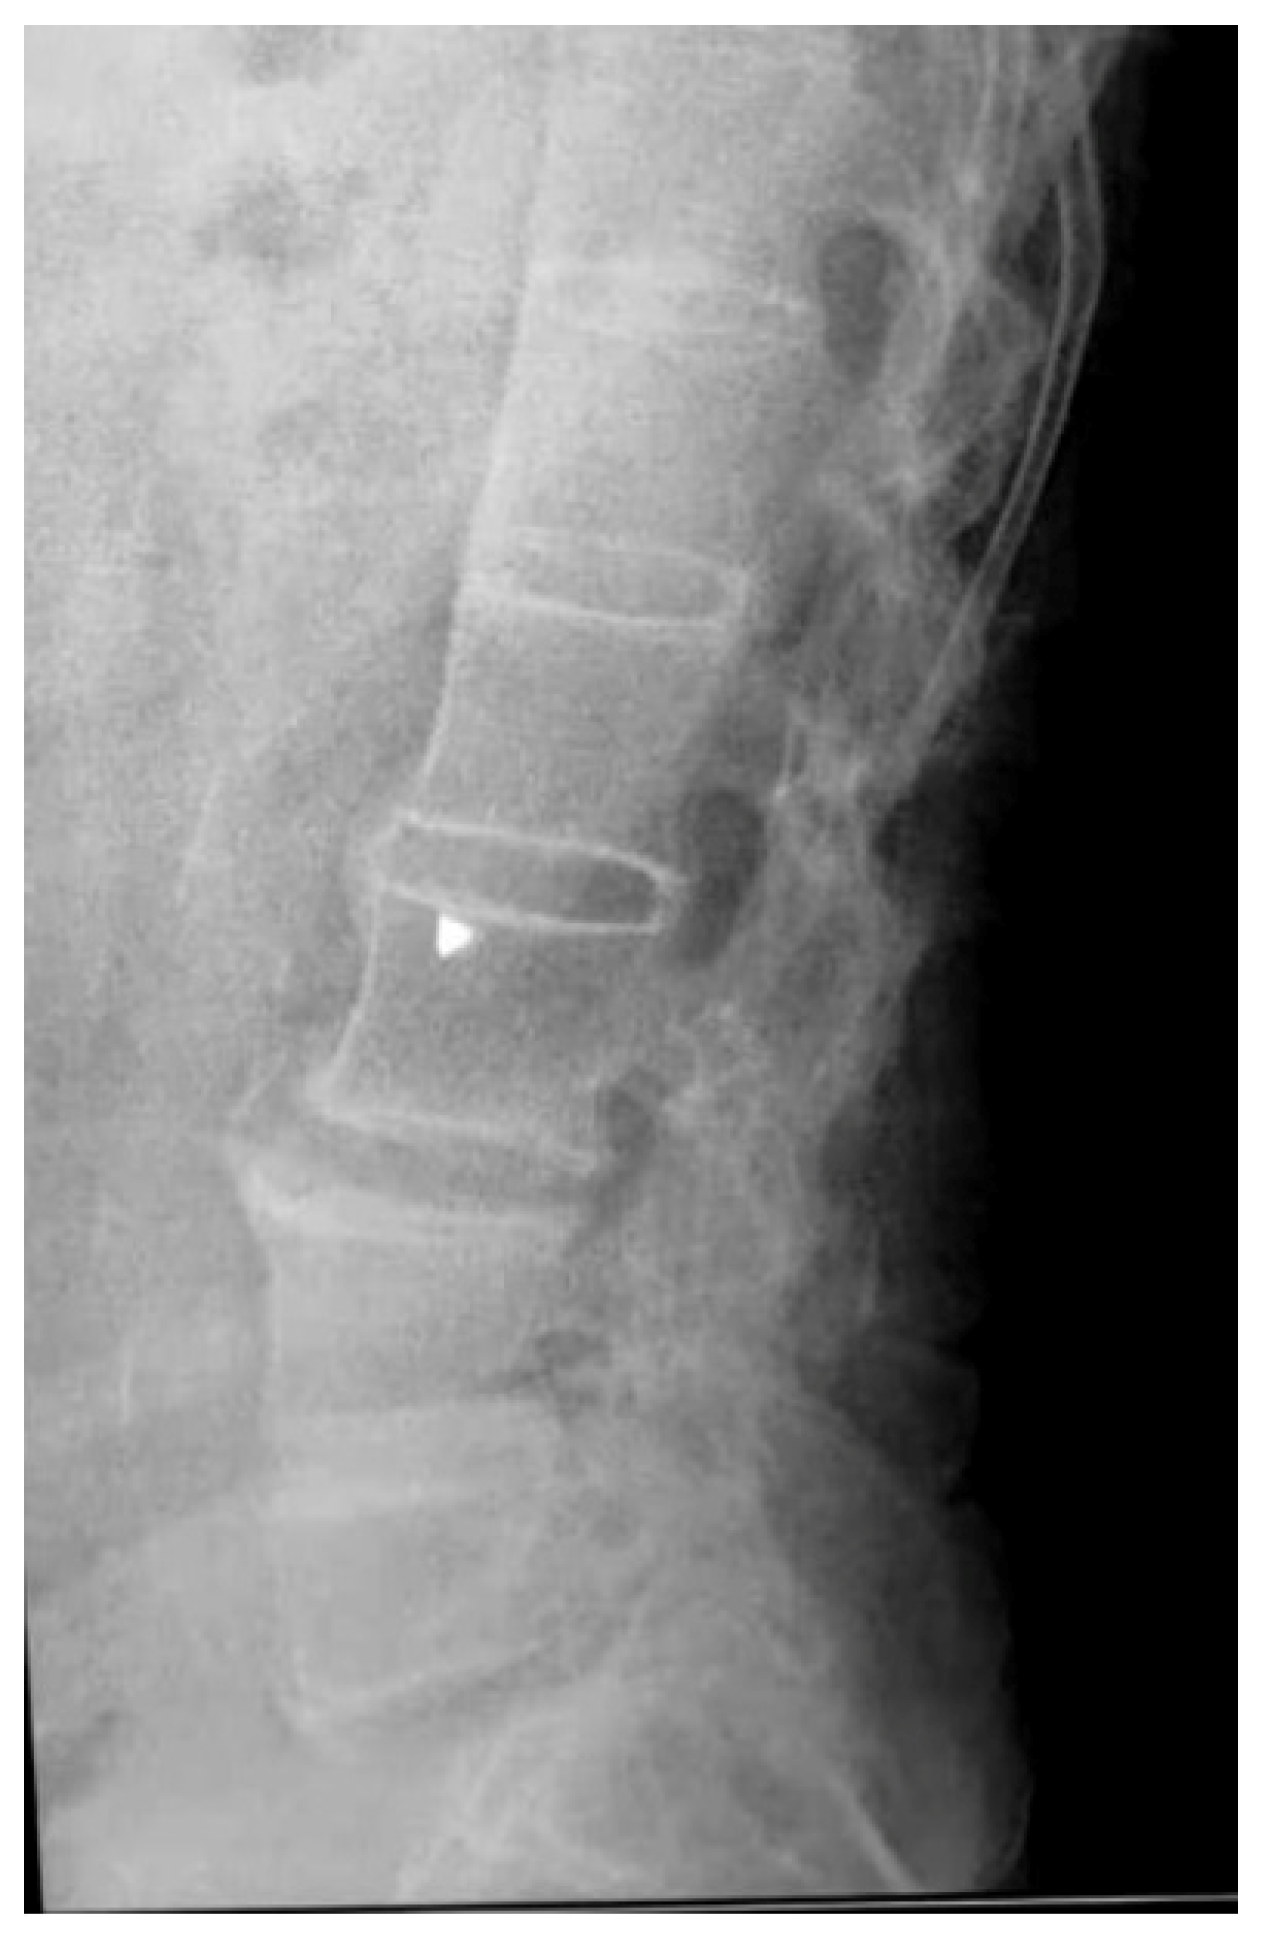

- Front and profile lumbar spine x-rays performed in the same year as normal follow-up investigations.

- No imaging of the lumbar spine.